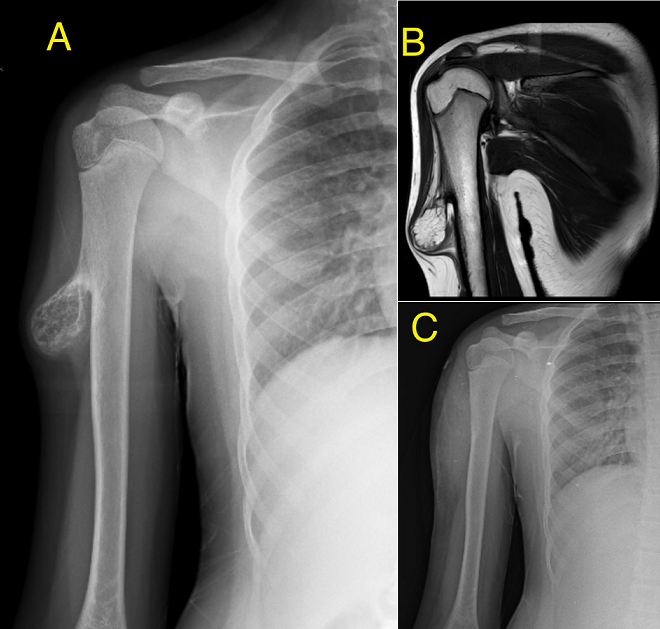

Pedunculated osteochondroma of right humerus

A 16-year-old boy presented with a painless, hard swelling over the lateral aspect of his right upper arm. There was no history of trauma, constitutional symptoms, or functional limitations. On clinical examination, the mass was firm and nontender. Radiography of the right upper limb revealed a solid, irregular outgrowth of the right humerus (A). Magnetic resolution imaging (MRI) revealed a bony outgrowth arising from the lateral aspect of the diaphysis of the right humerus, suggestive of a pedunculated osteochondroma (B). Owing to cosmetic concerns and the potential risk of neurovascular compression, surgical excision was performed. Histopathological examination confirmed a benign osteochondroma with no evidence of malignant transformation. The postoperative radiography revealed cosmetic improvement (C) and the patient remained asymptomatic. This case underscores the importance of recognising osteochondroma as a common benign entity in adolescents, while also considering the need for surgical intervention in symptomatic or cosmetic cases. Early imaging and appropriate management can prevent complications, particularly in lesions with atypical growth or proximity to vital structures.